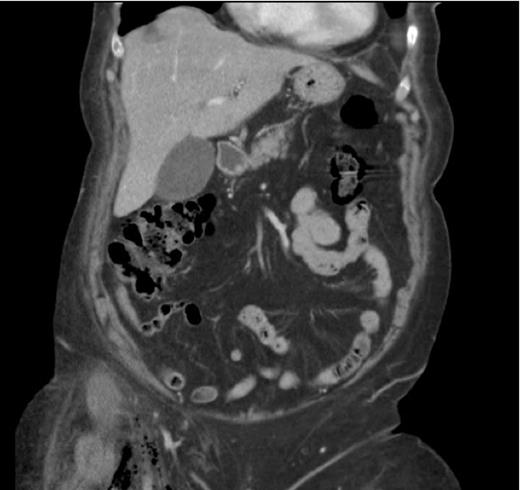

A 75- year old female was admitted as an emergency with right iliac fossa pain. She was afebrile. Bloods on arrival showed leukocytosis of 18.6 and CRP of 235.5. Clinical examination was inconclusive. During her over-night stay, she developed tachycardia and hypotension which responded to fluids. On review, abdominal examination revealed fullness in the right iliac fossa. More importantly she developed swelling and redness of the right thigh. The patient had a CT abdomen, pelvis and upper thigh that showed gas containing fluid collection in the right iliac fossa in keeping with either diverticular or appendicular abscess (Figure 1). It also showed inferior extension of the gas into the right ilio-psoas muscle, groin and upper thigh (perivascular) raising the possibility of necrotising fasciitis (Figure 2).